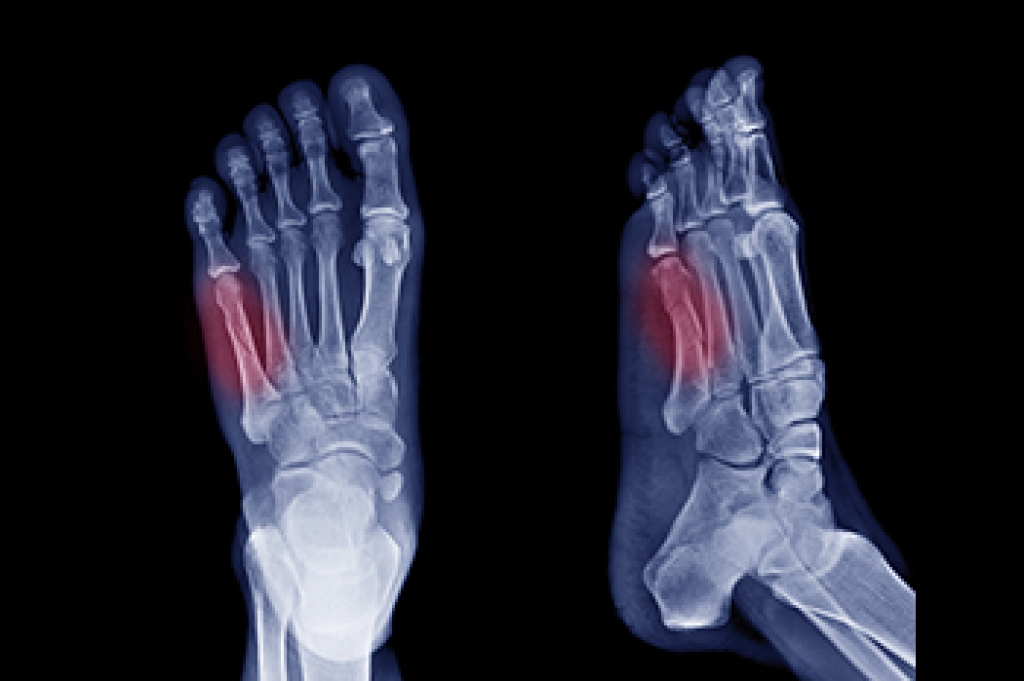

Podiatrists often perform two tests – blood tests and x-rays – when trying to diagnose bunions, especially in the early stages of development. Blood tests help determine if the foot pain is being caused by something else, such as arthritis, while x-rays provide a clear picture of your bone structure to your provider.